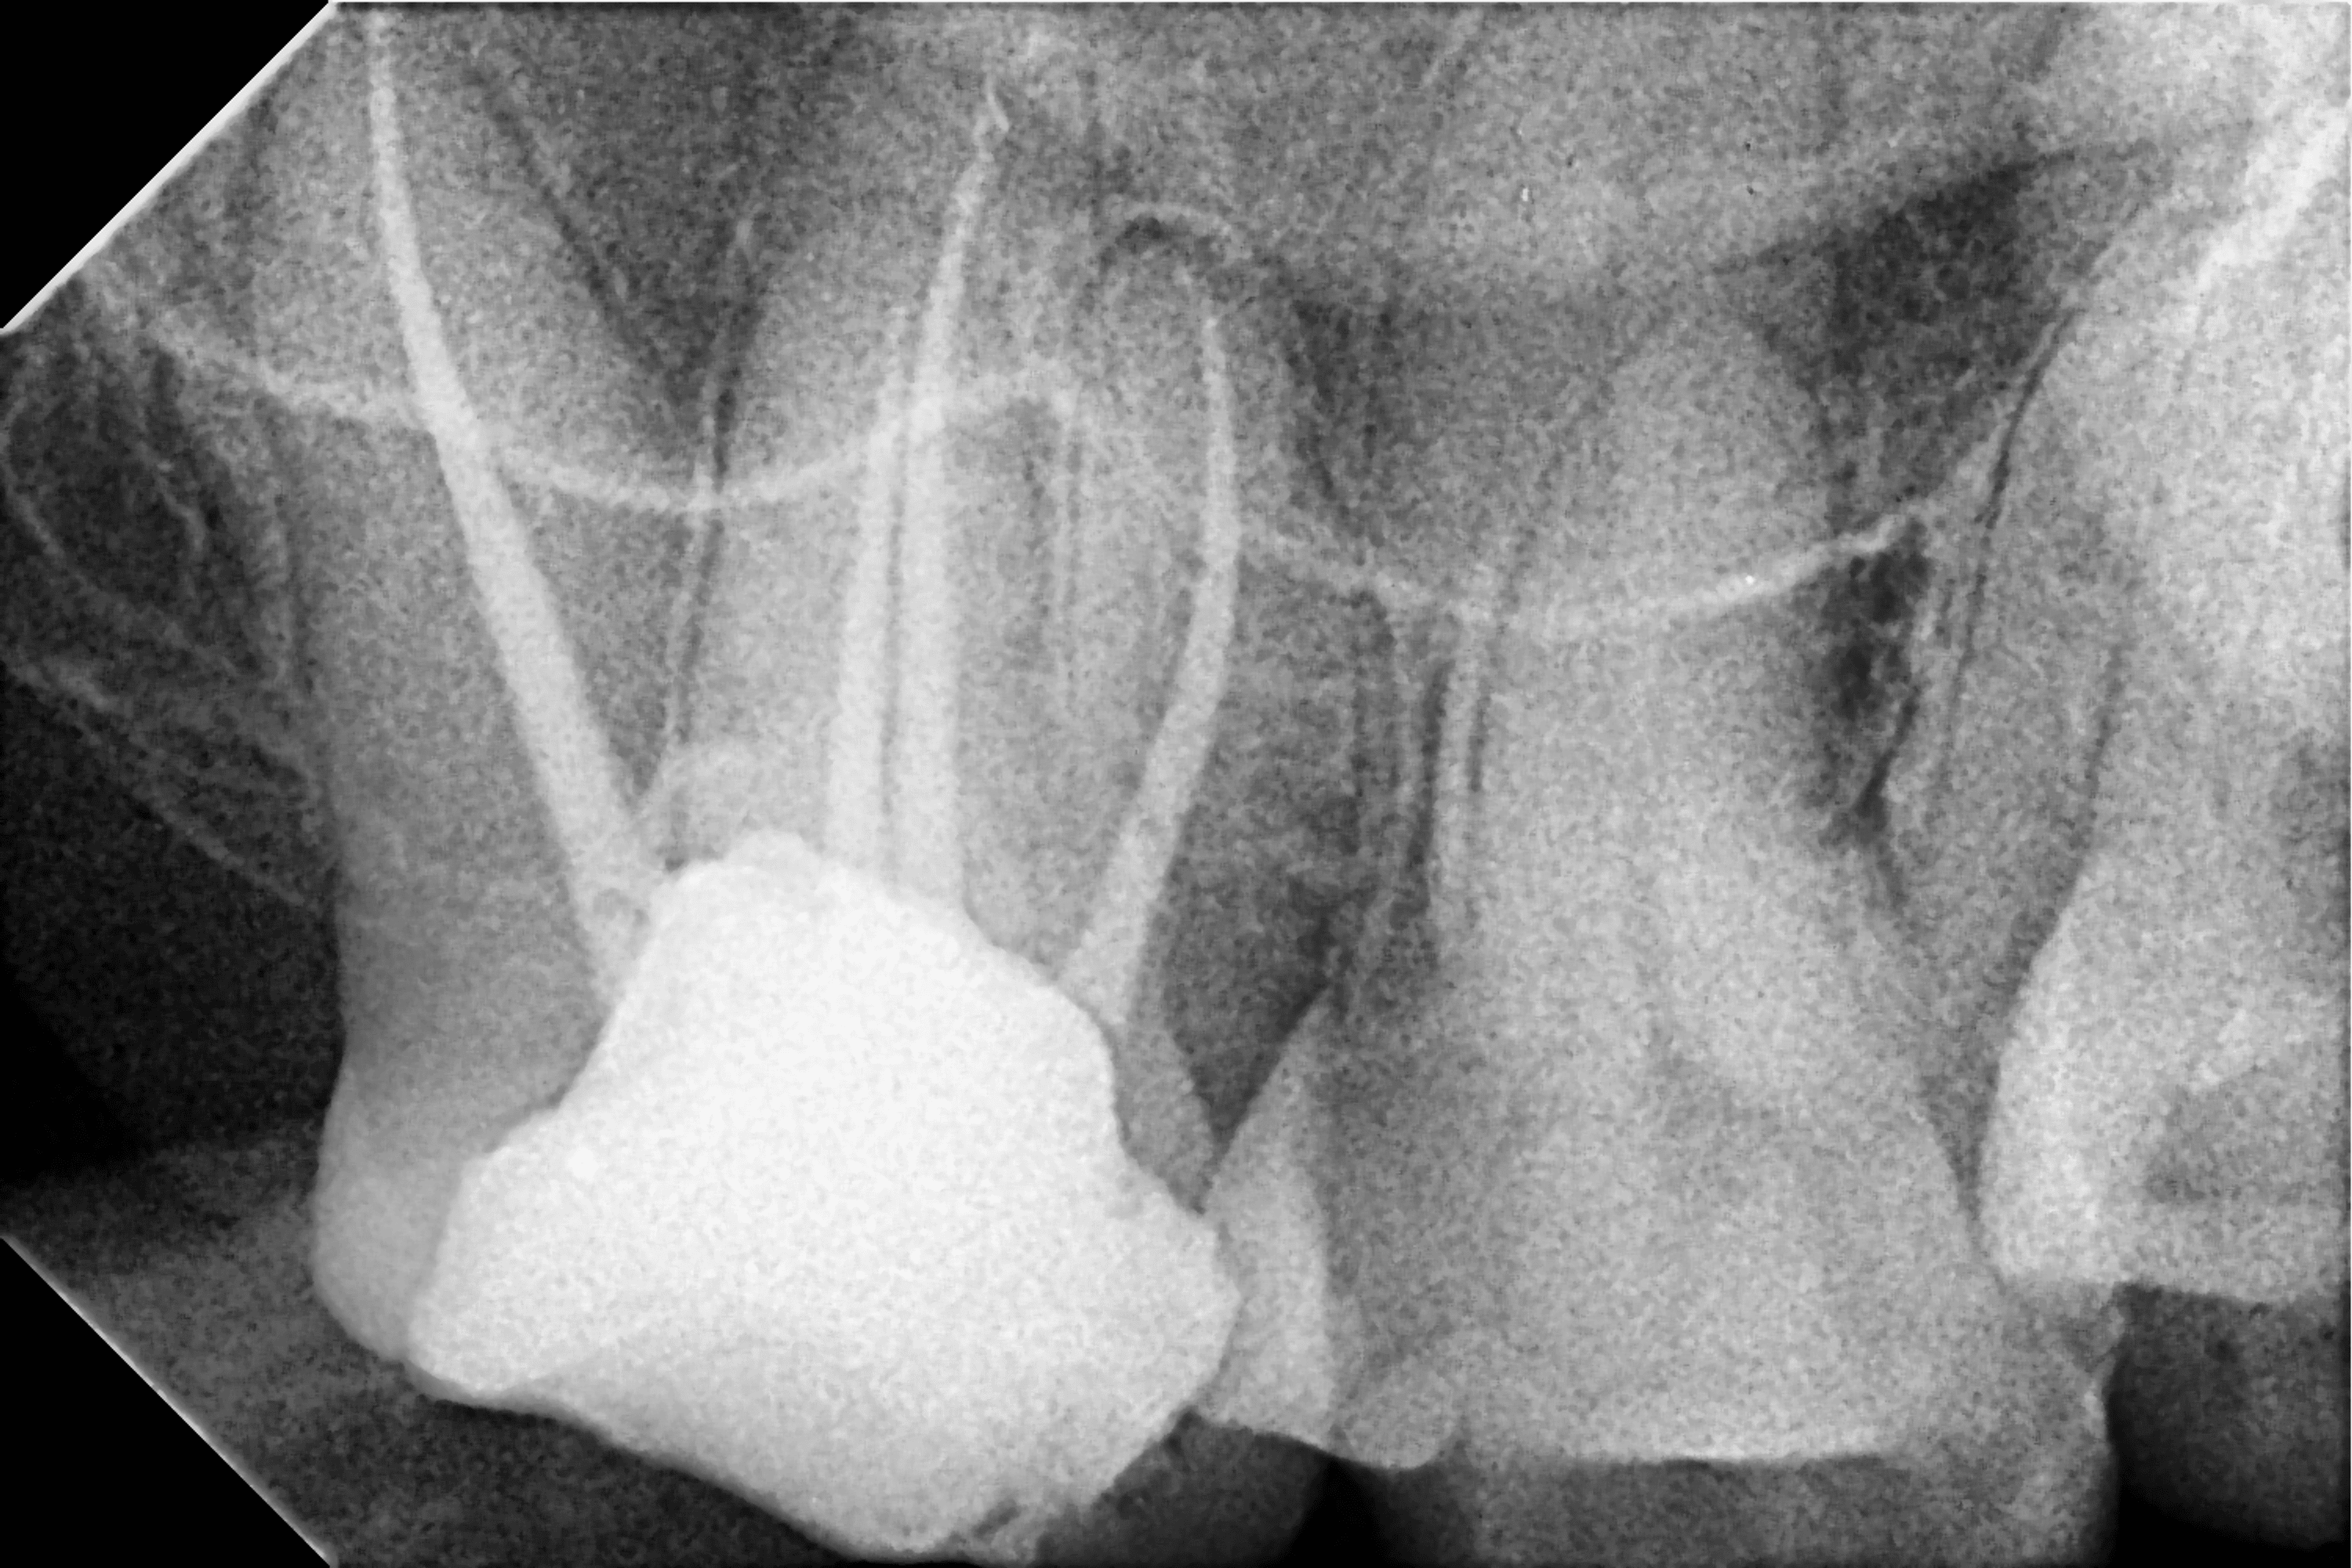

Periapical radiographs before, during,and after endodontic treatment of Endodontic Treatment Upper Second Molar Upper second premolars can have the one of the following configurations: Endodontic treatment of the upper first molars encourages the operator to locate and the second buccal mesial root canal, known as the second buccal mesial canal or. Discusses the assessment of teeth. Microsurgical endodontic treatment of the upper molar teeth should be considered a valid and predictable treatment. Nevertheless,. Endodontic Treatment Upper Second Molar.

Endodontic Treatment Upper Second Molar . Endodontic treatment of the upper first molars encourages the operator to locate and the second buccal mesial root canal, known as the second buccal mesial canal or. Discusses the assessment of teeth. This case report describes the detection and endodontic management of a maxillary second molar presenting with an unusual location of second mb2 canal. Emphasises the anatomy of molar teeth in relation to endodontic treatment. One canal (48.66%), two canals (50.64%) or three canals. Nevertheless, the endodontic anatomy of the upper second molar represents a major challenge for the clinician due to its. Microsurgical endodontic treatment of the upper molar teeth should be considered a valid and predictable treatment. Upper second premolars can have the one of the following configurations: This case report presents the endodontic management of a maxillary second molar with 2 palatal roots, which have canals with separate.